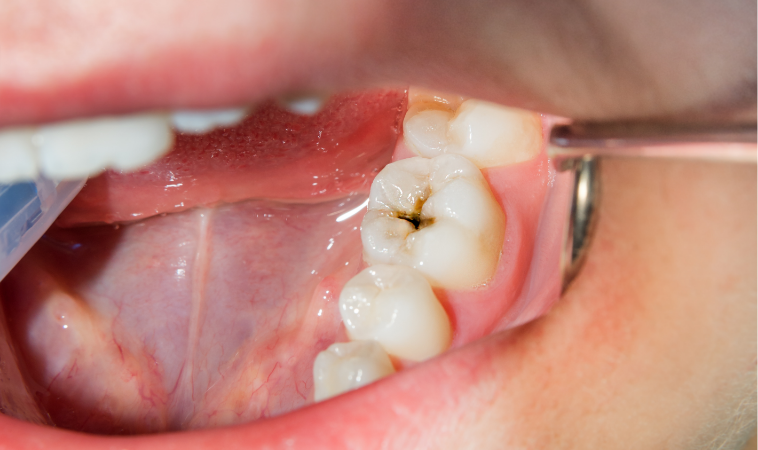

むし歯は、歯の表面にいる細菌が食品に含まれる糖を分解する際に作る酸で歯が溶かされてしまう不治の病です。

初期には痛みを感じませんが、放置すると歯が欠けたり、ズキズキとした激しい痛みを感じたりします。

| 症状 | 初期のむし歯 穴があく一歩手前 |

|---|---|

| 治療法 | クリーニングと定期観察、フッ化物入り歯磨剤の適正使用 |

| 症状 | エナメル質が溶け始めた小さなむし歯 |

| 治療法 | むし歯部分のみ最小限に削って詰め物をするか、削らずに自宅や歯科で予防処置を行い、むし歯の進行を防ぐ |

| 症状 | エナメル質の奥にある象牙質にまでむし歯が進行した状態 |

| 治療法 | 進行度合いを経過観察しつつ、部分的に削って詰め物をする |

| 症状 | 象牙質の奥にある歯髄という神経にまでむし歯が進行した状態 激しい痛みが発生する |

| 治療法 | 神経を除去し根管治療を行う※症状や病状、治療法の選択によっては神経を残せる可能性あり |

| 症状 | 完全に神経が死んでしまった状態、歯の根に膿がたまっている状態 |

| 治療法 | 抜歯が必要になるケースもあるが、特殊な治療法によって歯を残せる可能性もある |